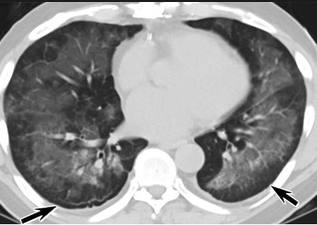

怎么“中度可疑”呢?這些專家表示,這5位患者的肺部CT都具備新冠肺炎CT的影像特征,比如肺部出現(xiàn)磨玻璃的影像,磨玻璃主要分布在雙下肺靠近外周,出現(xiàn)鋪路石征、嚴重的表現(xiàn)為雙肺彌漫性多發(fā)實變。同時,其病程轉(zhuǎn)歸和臨床特征也與新冠肺炎相似。

以下面這4張圖涉及的這個美國“電子煙”病人為例,專家不是僅僅通過一張影片做判斷的,而是通過這4張涵蓋了這名病例肺部多天變化情況的影片進行的研判,認為該病例的病程進展跟新冠更為相似。